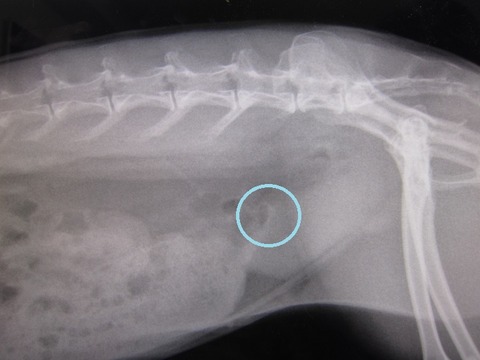

kagu0812

無いんちゃう?」

kagu0813

「な 先生、無いやんね無いやんね

というか、かぐらさんお腹周りが大きいなと思ってたら

脂肪も多いです…(。--)ノ (上下外側の色の薄い部分…)

ただ、強いてこじつけレベルで指摘するとしたら…こうゆう白い塊ね。

kagu0811

これは左右対象にあるから恐らく乳頭と思われる… それと、

kagu0810

…印付けに自信がないですが、薄いおはじきのような白色は写ってます。

上にいくと消化器官ですが、丸くなる手前かも、とかとか…

…ちょっとモヤっと感は残るんですが、

「喜んでも良いと思います」て言うてたから、喜んでいいんやと思います(^-^;)